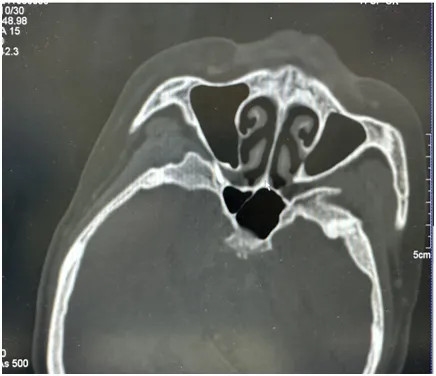

根治:这一次,她的疼痛局限在右侧上牙槽上颚区域,为了更少花费、更小痛苦、更快恢复,神经外科一病区决定利用

这种技术犹如导弹般精准打击造成李阿姨痛苦的神经。在CT引导定位下,进行圆孔穿刺,上颌神经射频治疗。

▲ 术中影像学图片

在寿记新主任的带领下,吴峰副主任医师的协作下,丁攀峰、程森、王冰冰医生在CT室对李阿姨进行了精准的治疗。幸运的是,经过三叉神经第二支射频术的治疗,李阿姨终于能够正常进食和安睡。不仅疼痛消失了,连“胃炎”引起的呕吐也好了,原来呕吐也与神经受刺激的反射有关。